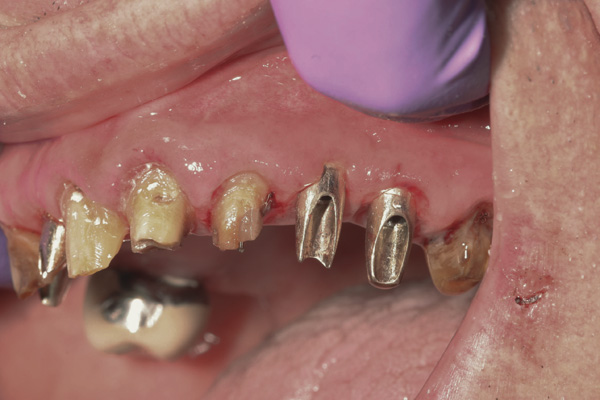

Results: A decision was made to re-prepare all of the abutments intraorally (Figure 3) so that all abutment margins would be at or below the gingival margin. (Of note, tooth Nos. 8 and 9, also shown in Figure 3, were later submerged for the case to be fully implant-supported.) While re-preparation greatly improved the esthetics of the final result, it required retraction cord placement, new impressions, and new castings.

(Note: A separate but similar type of case shown in Figure 4 and Figure 5 further illustrates intraoral abutment re-preparation.)

Figure 3 Abutments re-prepared intraorally.

Figure 3

Figure 4 Following osseointegration of an implant at No. 12, recession was observed at the fixture-level impression stage of No. 13; it was decided to re-prepare the margins of the CAD/CAM custom abutment of implant No. 12. Retraction cord was placed prior to preparation to avoid tissue injury and improve visibility of both tooth No. 11 and the implant custom abutment margin. As expected, recession was greater along the distal side of abutment No. 12, adjacent to the healed extraction/newer implant site.

Figure 4